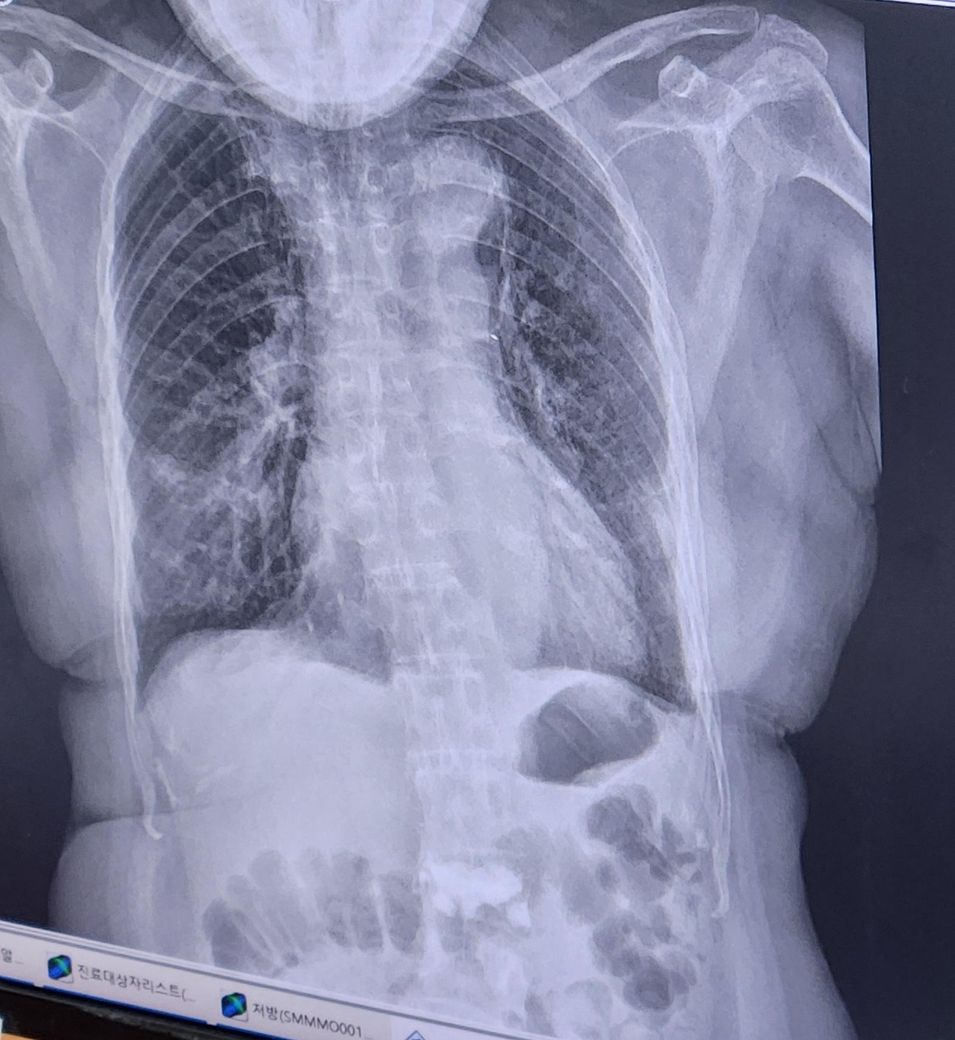

폐렴 입원문의 중증도 인지 궁금합니다

기침가래콧물있음/가래노랑색/발열없음

산소포화도96/네블약 처방받아 치료중입니다(벤토린 플마코트)

폐렴의 중증도와 입원 여부는 환자의 상태, 기저질환, 증상 정도에 따라 달라집니다. 현재 산소포화도가 96%로 정상 범위에 가깝기 때문에, 입원치료가 필수적이지는 않을 수 있습니다. 하지만 기저질환인 고혈압 등도 고려해야 하므로, 담당 의사의 판단을 받는 것이 중요합니다. 산소포화도가 90% 이하로 떨어지지 않으면 중증으로 분류되지는 않지만, 폐렴의 치료는 상태에 따라 2주 정도 걸릴 수 있어요

통원치료도 가능할 수 있으나, 치료 후 상태가 안정될 때까지는 입원이 필요한 경우도 있습니다. 가래의 색이 노란색인 점은 염증을 나타내는 것일 수 있으므로, 이를 토대로 추가적인 치료가 필요할 수 있죠. 중증 폐렴의 경우 산소포화도가 낮아지고, 호흡이 어려운 상태가 될 수 있기 때문에 미리미리 담당 의사와 상담해 치료 계획을 세우는 것이 좋습니다